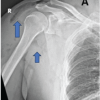

A 45-year-old healthy man with no significant medical history presented to the emergency department after new-onset seizure, he had complaints of post-ictal confusion, irrelevant talks, and pain over both shoulder and upper back. On examination, he had an improving post-ictal state, tenderness on palpation, and movement of both shoulders, greatest posteriorly. The patient was investigated for complete blood count, urine R/M, coagulation profile, serum electrolytes, random blood glucose, serum calcium, serum inorganic phosphorus, alkaline phosphatase, 25-hydroxy Vit. D, magnetic resonance imaging (MRI) brain, and electroencephalogram (EEG) with sleep record. Investigation reported hypocalcemia (Ca2+: 8.00 mg/dL and 25-Hydroxy Vit-D: 10.60 ng/mL). The patient was further assessed with X-ray of scapula which revealed comminuted fracture of the body of both scapula and computed tomography (CT) with 3D reconstruction confirmed fracture of the neck and body of the bilateral scapula (Fig. 1).